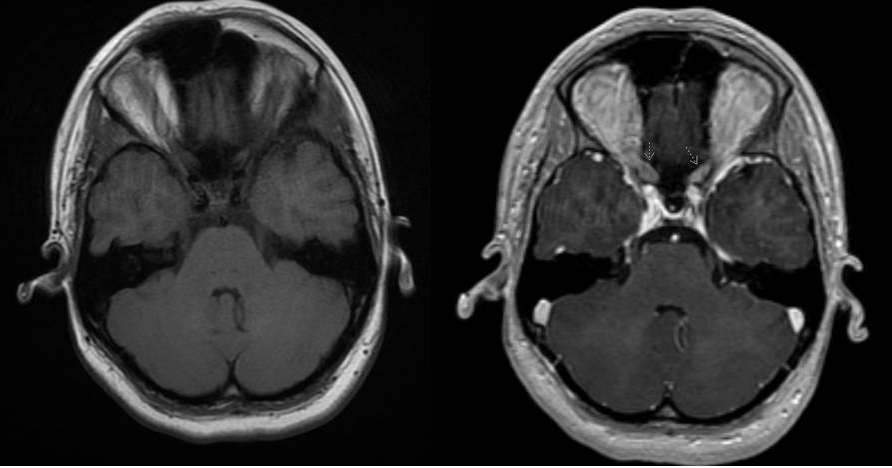

An MRI of the Brain and orbit with and without contrast as well as fat suppression can enhance the involved optic. However, as the image through the optic chiasm may be limited to one slice, pathology may be overlooked.[2] Therefore, it is important to specify that small cuts3T (3mm or less) are needed. Additionally, early on MRI cannot differentiate RON from a recurrent tumor.[4] Communicating the clinical presentation to the radiology specialist may yield to a more efficient location of the pathology.